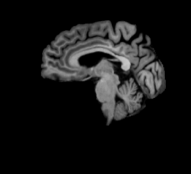

In this study, we use the baseline 1.5T T1-weighted MRI images of subjects from the ADNI-1 dataset [10]. The volumetric 3D MPRAGE protocol is used to acquire sagittal T1-weighted MRI images with an in-plane spatial resolution of 1.25×1.25mm21.251.25superscriptmm21.25\times 1.25~{}\mathrm{mm}^{2} and 1.2 mm thick sagittal slices. The imaging dataset contains baseline images from 695 participants including 200 Alzheimer’s disease, 231 cognitively normal, 164 progressive MCI, and 100 stable MCI. Figure 5 shows four samples from this dataset, and Table 1 presents the demographic and clinical information of subjects in ADNI-1.

Figure 5: Four samples from ADNI-1 dataset [10] (a) AD, (b) CN, (c) pMCI, and (d) sMCI